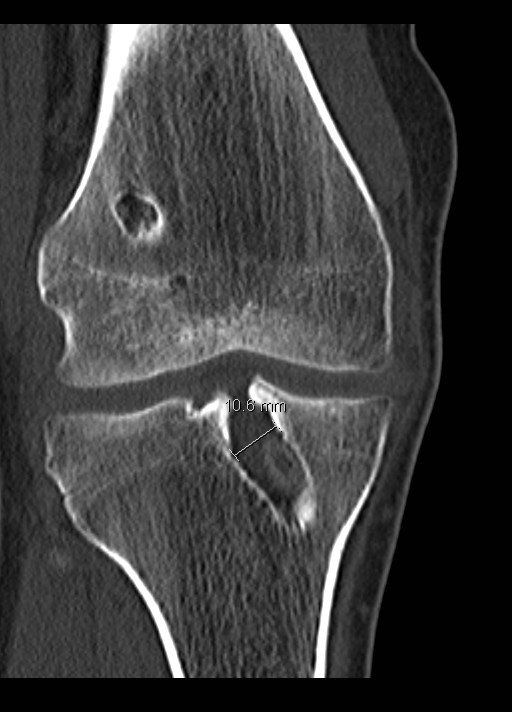

- CT scan:

- Pending on size and location of tunnels on X-rays, CT scan is often required

- This will help provide more detailed information on the size and position of the tunnels which is the key determinant whether revision ACL reconstruction can be performed in one sitting or two

- Tunnel dilation (see below)

- Tunnel dilation:

- The tunnels when they are drilled are cylindrical in nature

- Over time the tunnels may dilate and increase in diameter especially in between the apertures i.e. section between the entrance and exit of the bony tunnel in the femur and tibia

- If this dilation is >10-12mm in diameter then performing the operation in one sitting is more problematic as the tunnel will be bigger than the graft leading to problems with position, fixation and loosening:

- In this scenario (especially for tunnels much bigger than 10mm) it would be better to perform the revision in two stages: